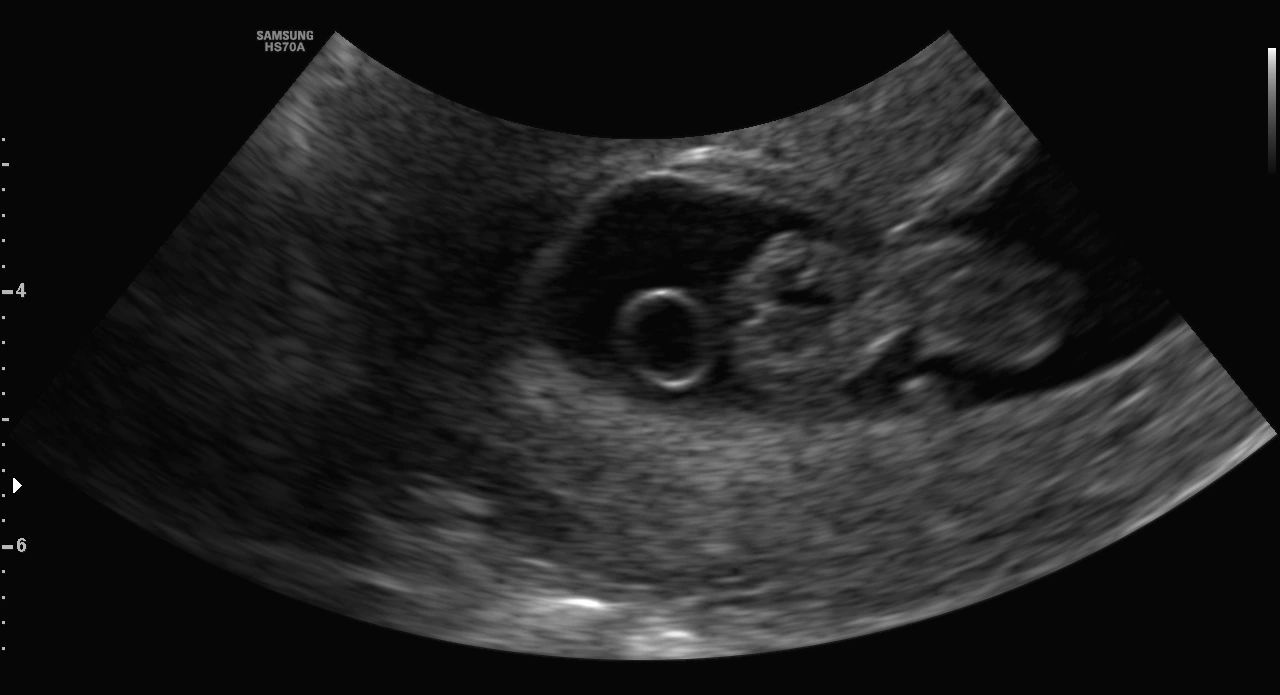

두 번째 콘텐츠: 초음파 사진에서 숨은 아기 찾기

임밍 아웃 이벤트가 끝날 무렵 초음파 이벤트가 다가왔다.

우리는 초음파 사진에서 아기집을, 천사 고리를, 젤리 곰을, 사람을 닮아가는 형체를 찾느라 매일 들떠있는 시간을 보냈다. 시간이 흐름에 따라 나의 초음파 보는 실력도 늘었다.

KakaoTalk_Photo_2024-07-28-12-24-16.jpeg 이쯤 많이들 찍는 아기 천사 사진

특히 태동이 있기 전까지는 초음파로만 아이가 잘 지내는지 알 수 있었기 때문에 초음파 사진을 보는 게 정기 이벤트로 자리 잡았다. 그리고 태동이 시작되면서 초음파 이벤트에 대한 열기는 숨은 아기 찾기보다는 잘 자라고 있는가를 측정하는 목적으로 변화하게 된다.